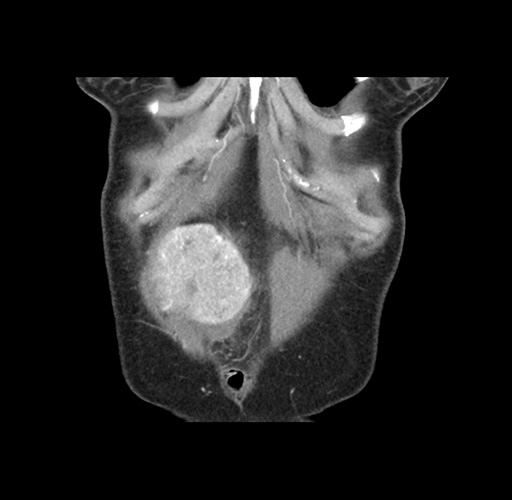

Imaging Analysis

Look through the patient's CT scan to identify any areas of concern for the necessary procedure.

Based on your CT findings, which issue(s) would give reason for "planned slowing down moment(s)" in this case?